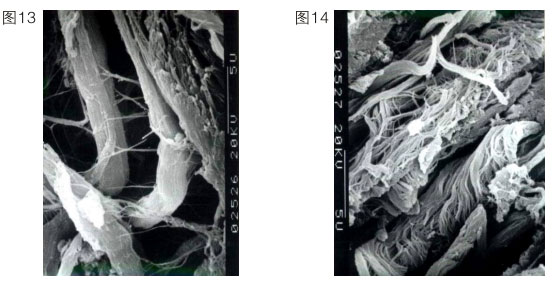

上述内容说明再生复原重要的是要恢复其皮肤正常的生理功能。正常人的皮肤衰老了,意味着他皮肤的很多功能缺失了或退化了。因此我们的皮肤再生必须控制细胞,让细胞强壮,恢复正常生理功能。我们在实践中就启动了角蛋白十九型干细胞,当然也可以启动角蛋白十九型以下的细胞。我们首先把表皮基底层细胞启动起来,使它可以增加生命活力,重建,同时成纤维细胞也更新。一个90岁的老人,基底细胞只有5%是有功能的。人一旦衰老了,细胞就难以再生到足够的数量,所以一定要保证再生物质的量,确保细胞的功能。一般来说,成纤维细胞的功能,随着年龄的增长会代谢低下,这个低下指的是产生纤维的速度减慢、产生的量减少,产生的胶原纤维不成束。一个正常细胞产生的纤维如左图所示(图13),一个衰老的细胞产生的纤维如右图所示。(图14)这个衰老的细胞产生的丝是杂乱无章的,没有弹力,又散又少。人老了,在细胞里产生的原纤维

就杂乱无章,成纤维细胞吐出来的纤维也就不成束了。所以他的皮肤组织里面就是空洞的,皮肤就不紧致。我们再生物质的功能就是要把这种细胞不正常的功能纠正过来。我们要增加细胞的活性。皮肤真皮的丰满程度,是靠成纤维细胞活力的增强来实现的。在活力没有增强之前先把产生的纤维成束,一边成束,一边更新。这样就出现一个保持年轻复原状态。这个皮肤再生复原的时间问题涉及代谢时间问题。表皮的创伤性修复速度快,一般7天修复完成。一个正常人的表皮生理代谢,则是7天一层,基底层到角质层是30层细胞,三七二百一十天。一个完全晒黑的人经过210天可以复原回原来的颜色。皮肤表面的黄褐斑、老年斑我们都可以解决,但不是用激光、光子消掉就可以了,这样还会再长,因为是细胞的异常属性没变。我们是用再生改变这个细胞的异常属性,激活二次生命细胞,使皮肤再生复原。